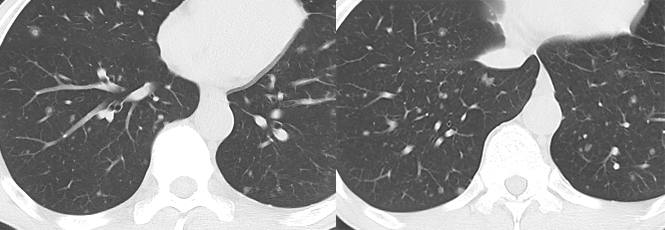

空洞性肺转移瘤

文献报道空洞型肺转移主要来自鳞癌和腺癌,鳞癌占 1/2-2/3,主要来自男性头颈部与女性生殖器肿瘤,其余为腺癌,主要来自结肠与乳腺癌。单亦有研究认为空洞性转移主要来自腺癌。其产生机制可能与鳞癌中心角化物排空、腺癌黏液样退变后黏液排空、肿瘤血供不足引起坏死、肿瘤继发脓肿、化疗、阻塞性肺气肿等有关。空洞性肺转移瘤变化快,短期内可见肿瘤增大、增多。CT 上空洞型转移结节外形上多保持了转移瘤的基本特点,即多发、圆形、边缘光整。洞壁多薄而均匀,内外壁光整,直径多 <1.0 cm,部分洞壁厚薄不均,厚壁空洞病变可随着病灶增大而出现分叶、毛刺及壁结节等恶性空洞特点,部分空洞型肺转移洞壁可菲薄(称空泡更合适)。

乳腺癌空洞性肺转移。

54 岁男性,肾癌病史。左肺下叶厚壁空洞性转移(穿刺证实),左肺另见不伴空洞的实性小结节转移灶。

男,63 岁。食管鳞癌术后 3 年,痰中带血丝半年。穿刺证实双肺多发空洞和空泡转移,周围磨玻璃密度是转移瘤引起出血。